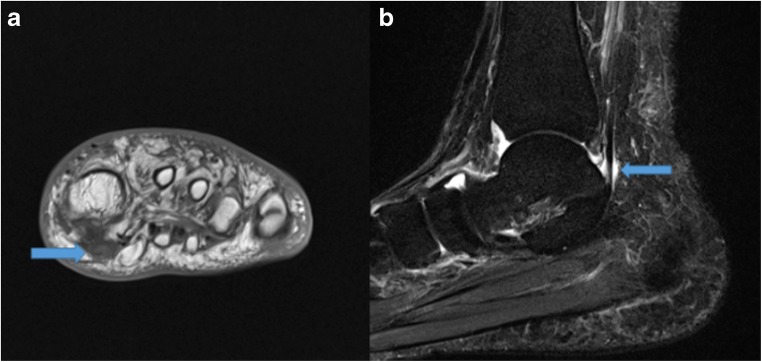

MRI provides superior soft tissue resolution and multiplanar capability to illustrate FHL tendinopathy and commonly associated posterior ankle impingement syndrome (PAIS). PAIS causes limited range of motion, specifically limited ankle plantarflexion as a result of soft tissue or bone impediment [62, 70]. MRI can delineate the posterior capsular thickening and enhancement within the musculotendinous junction of the FHL muscle belly [62]. Additionally, FHL tendinopathy can be diagnosed by visualization of an abrupt cessation of fluid around the FHL tendon at the level of the posterior talus (Fig. 9a, b) [62].

Fig. 9.

Coronal T1-weighted (a) image demonstrates increased signal within an enlarged flexor hallucis longus (FHL) tendon near its insertion (arrow), indicative of FHL tendinopathy. Sagittal T2 short-tau inversion recovery (STIR) (b) image demonstrates irregular, lobulated fluid in the proximal FHL tendon sheath (arrow) indicative of mild tenosynovitis.

Conservative treatment focuses on rest, ice, NSAIDs, physical therapy to mobilize the FHL tendon, and steroid injections. Surgical tenolysis, pursued after 6 months of failed conservative management, provides satisfactory outcomes in 89% of cases and an average period of return in dancers at 16 weeks [70, 71, 76].